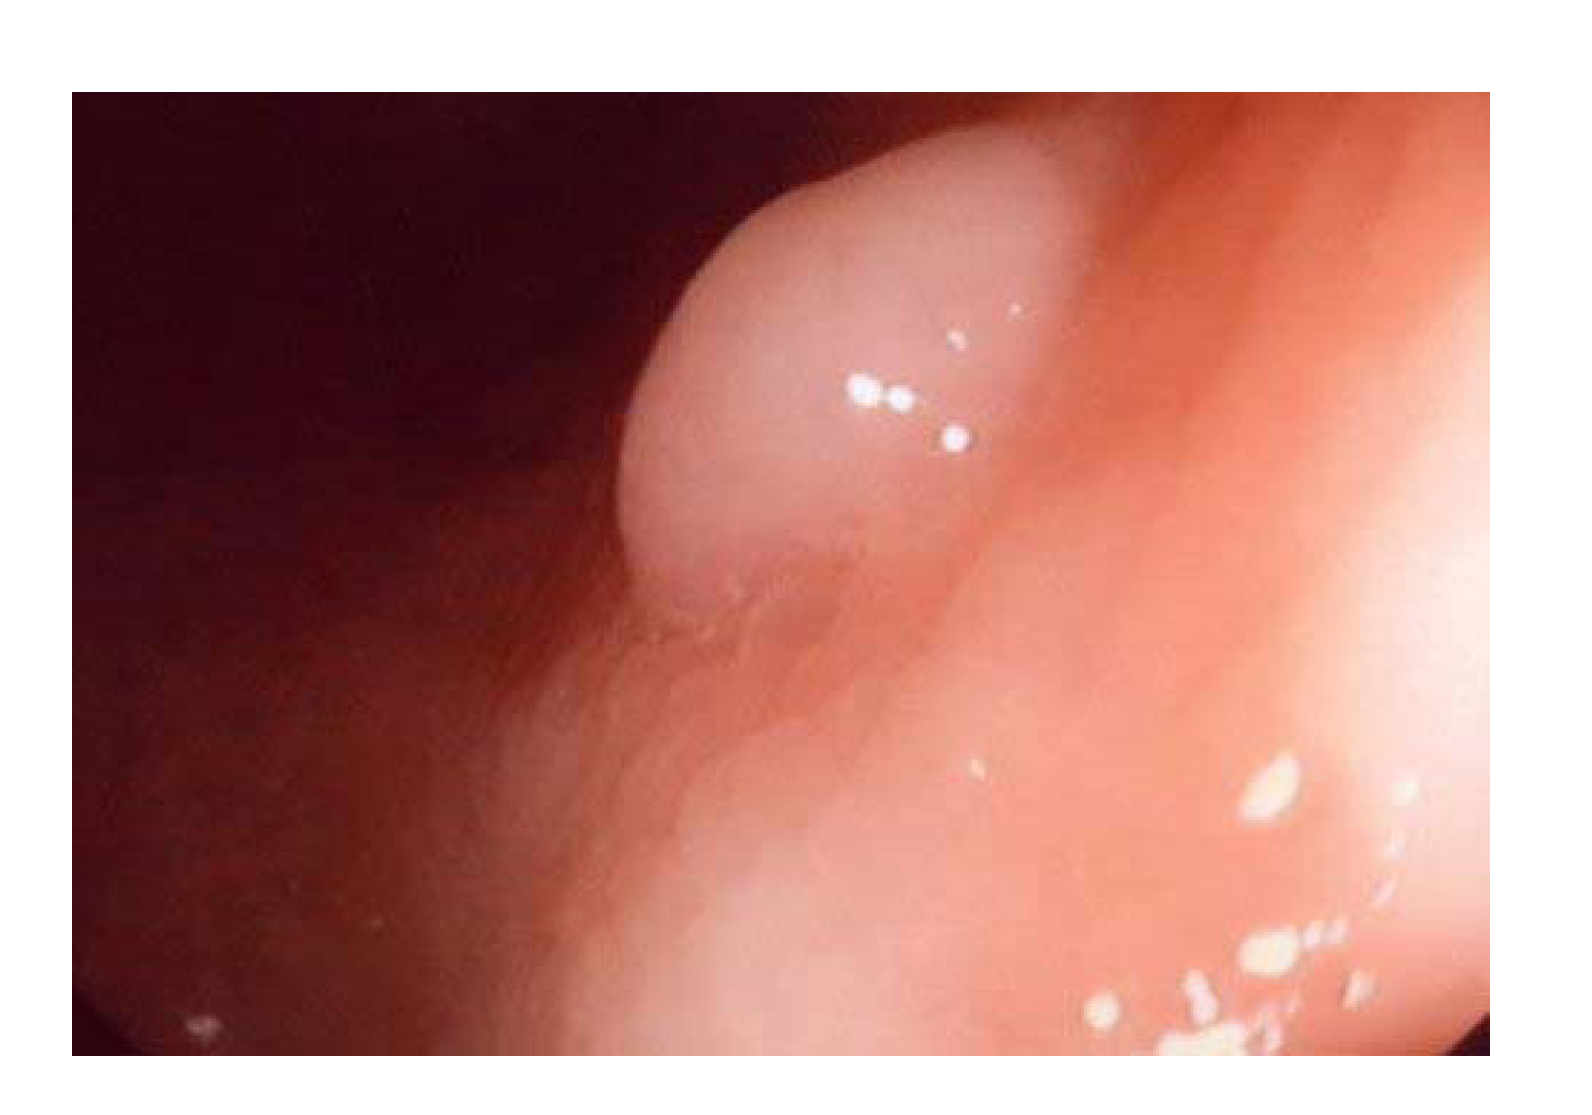

However, to apply photometric stereo in monocular capsule endoscopy, there are two key problems to be solved. First, the object surface for endoscopy, i.e., the digestive tract, is not an ideal Lambertian surface. As shown in Figure 1, specular highlights always exist in the captured images; thus, photometric stereo cannot be applied directly for such object surfaces. Second, to reconstruct the depth map of the whole object surface with photometric stereo, the ground truth of the depth of at least one object surface point is needed to serve as a boundary condition.

Figure 1. Digestive tract surface showing the specular highlight when illuminated by a light source from a certain direction.